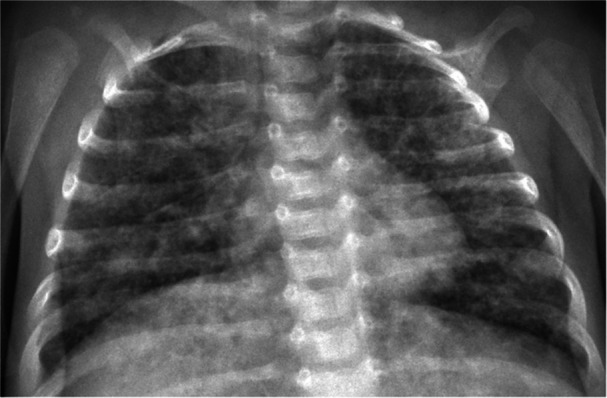

Background: We report a 1-month-old infant admitted with fever, dyspnea, and desaturation after an unmonitored pregnancy in a migrant family. The patient rapidly required mechanical ventilation. Laboratory parameters were markedly elevated, suggesting an infectious etiology.

Methods: The clinical course is described with emphasis on diagnostic challenges, including imaging, laboratory findings, and the stepwise process of differential diagnosis.

Results: After common etiologies were excluded, rarer causes were considered. The final diagnosis was established through integration of clinical assessment, radiological imaging, laboratory data, and microbiological testing.

Conclusion: In neonates with fever and respiratory distress, RSV bronchiolitis is usually the first consideration. If excluded, clinicians must remain alert to less frequent etiologies. This case underscores the importance of a broad differential diagnosis in infants with acute respiratory compromise.